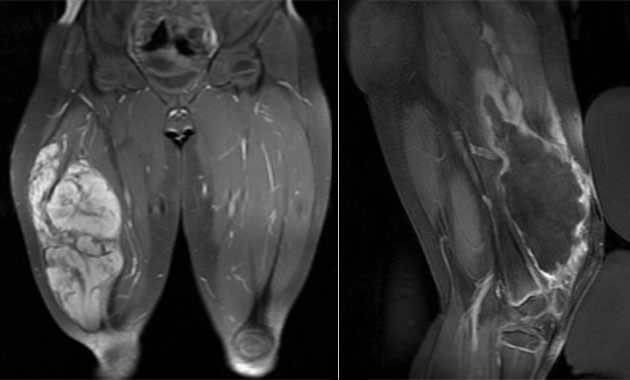

- Desmoid tumors

HIFU is FDA-approved for treatment of metastatic bone pain. UCSF offers clinical treatments for bone metastases and desmoid tumors which are billed to patient insurance.

We also have two ongoing clinical research trials for patients with osteoid osteomas and undifferentiated pleomorphic sarcomas. For more information regarding these two research trials, please contact our Clinical Research Coordinator, Maya Aslam at [email protected].